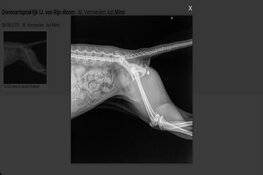

Vermeulen dacht dat Mimi was aangereden of gebeten door een hond en belde direct de dierenarts. Daar kon ze gelijk terecht. "Al snel zag dat de dierenarts dat ze een rond gat in haar pootje had en dat ze dus waarschijnlijk was beschoten. Vervolgens lieten ze foto's maken en daarop zie je duidelijk dat de kogel nog vastzat in haar pootje."

Kogel verwijderen

Omdat Mimi niet nuchter was, kon de kogel niet direct worden verwijderd. "We kregen pijnstillers mee, maar ze heeft vannacht heel veel pijn gehad. Ze heeft de hele nacht in onze armen gelegen in bed." Vanochtend bracht Vermeulen haar opnieuw naar de dierenarts om de kogel te laten verwijderen. "Ik mag haar zometeen weer ophalen. Volgens de dierenarts maakt ze het nu goed."